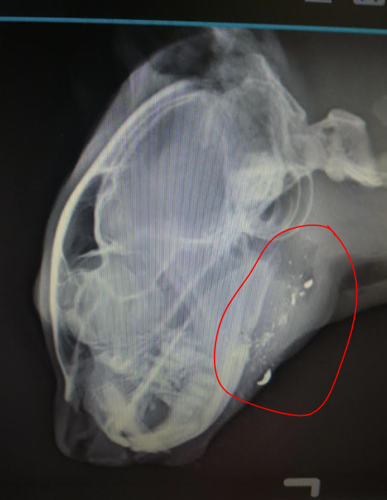

Donations Sought For Surgery On Cat With Buckshot In Its Face News Dailyindependent Com